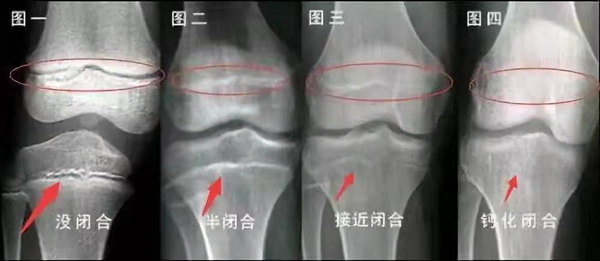

我們都知道,人體的高矮是由骨骼的生長(zhǎng)發(fā)育決定的,特別是下肢長(zhǎng)骨。長(zhǎng)骨呈長(zhǎng)管狀,在長(zhǎng)骨的兩端有一種專管骨骼生長(zhǎng)的骺軟骨,它與干骺端之間有一盤狀軟骨結(jié)構(gòu)稱為骺板(線),在幼兒的X光片上表現(xiàn)為一條較寬的透光帶。 (見下圖)

未成年時(shí)隨著年齡的增加骺軟骨端不斷骨化,骨骼就不斷增長(zhǎng)。當(dāng)骨骺線完全閉合時(shí)骨骼就停止生長(zhǎng),個(gè)子也就不再增長(zhǎng)了。一般骨骺端完全閉合的年齡是18~20歲左右。

青少年一般什么時(shí)候骨骺閉合?

一般女孩是在16歲,男孩是在18歲。

一般來(lái)說(shuō),女孩的骨齡超過14歲,男孩的骨齡超過16歲,這時(shí)其骨骺線已接近閉合,基本沒有長(zhǎng)高的機(jī)會(huì)了。

因此,越早了解骨骺線閉合情況,越早干預(yù),孩子長(zhǎng)高的可能性越大。